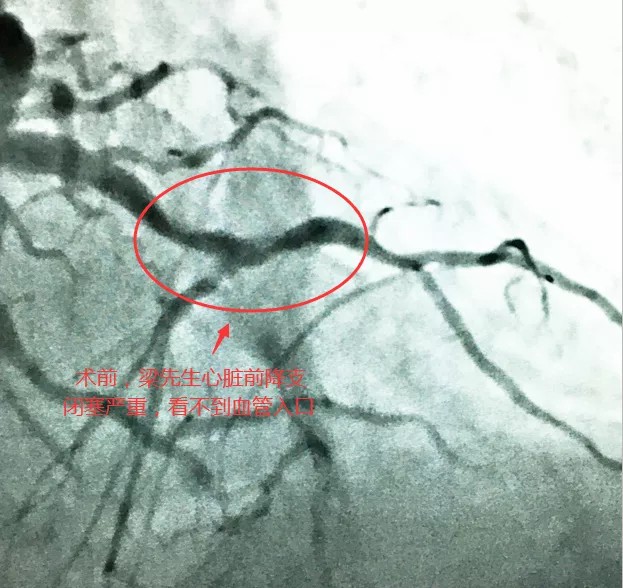

3月8日,63岁的梁先生因急性心力衰竭入院,梁先生既往有2型糖尿病、高血压病史,住院期间出现急性肺水肿和心源性休克,病情危重。医生检查发现梁先生患严重三支病变与前降支慢性闭塞。经治疗,初步控制了梁先生心衰病情,但改善其远期心功能必须进行冠脉血运重建。

经研讨,心血管内科团队一致认为梁先生前降支闭塞后形成侧支循环,有开通闭塞前降支的适应症,但用传统的前向导丝方法治疗成功率很低,且其病变复杂、基础病多,稍有不慎会有生命危险。经研究,心血管内科团队决定打破常规,采用同侧逆向导丝方法,由于操作导丝需谨慎不可破损心脏血管,这种治疗方案对主刀医生的综合要求很高。